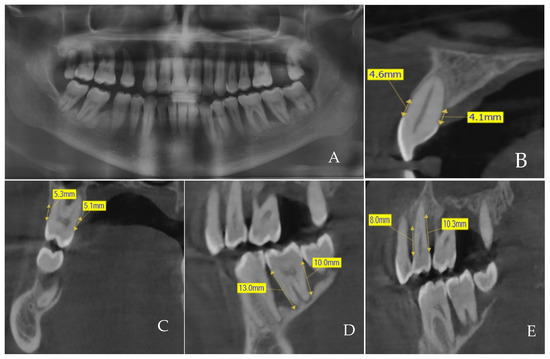

2.3. Acquisition and Measurements of CBCT Images